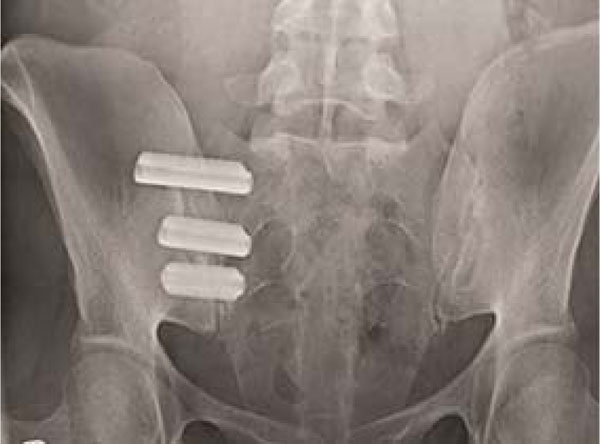

Sacroiliac Joint X Ray. Sclerosis of the endplates particularly on the iliac side. This view is useful in visualising any fractures, sacroiliac joint dislocations or subluxations, and possible inflammation (i.e.

Patient in semi supine position on the table. These features being sclerosis (thickening of the adjacent bone), erosion (irregularity of the bone) and joint space narrowing. The joint is difficult to profile well on radiographic views, and therefore the radiographic findings of sacroiliitis are often equivocal.

As sacroiliitis progresses the sacroiliac joints may widen and the articular surfaces become sclerotic Hover on/off image to show/hide findings. 10 x 12 film 2.

The sacroiliac (si) joint has several unique anatomical features that make it one of the more challenging joints to image. Minimum abnormality (small localized areas with erosion or sclerosis, with no alteration in the joint width) grade iii: Sclerosis of the endplates particularly on the iliac side.

Sacroiliitis grading can be achieved using plain radiographs according to the new york criteria 1,2. This is in contrast to spinal radiography which, however, has been recently included in a core set of outcome items to be assessed in clinical studies. Computed tomography images can usually show the findings of sacroiliitis and.